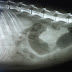

Enfermedad conocida con multiples nombres (Legg-Perthes, Osteocondritis juvenil, necrosis avascular de cabeza femoral) Es una necrosis aseptica no inflamatoria de cabeza y cuello de femur de perros de razas pequeñas casi en la totalidad de las ocasiones. La etiologia es desconocida, aunque es resultado de una isquemia postraumatica, con componente hormonal y genetico. El resultado es la necrosis dela cabeza femoral con colapso del hueso subcondral, deformacion de la cabeza e incongruenca articular, produciendo cambios degenerativos graves en toda la articulacion coxofemoral.

Radiologicamente Hay una radiotransparencia por perdida de material oseo en cabeza y cuello de femur finalizando con un colapso de la cabeza femoral.